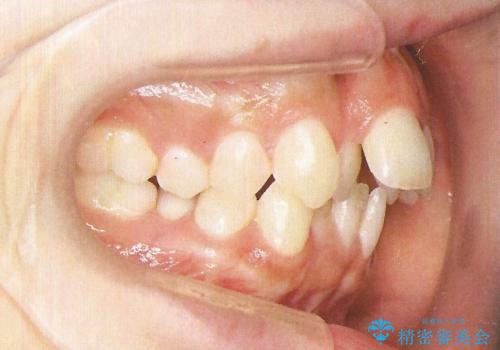

インビザラインで出っ歯を改善する 抜歯をしないinvisalign治療

- 非抜歯・遠心移動による前突の改善をマウスピースにて計画した。

非抜歯矯正の場合、大きく前歯を下げることはできませんが、奥歯の遠心移動や歯のサイズダウンにより歯軸を立て、見かけ上の出っ歯感をある程度改善することができます。